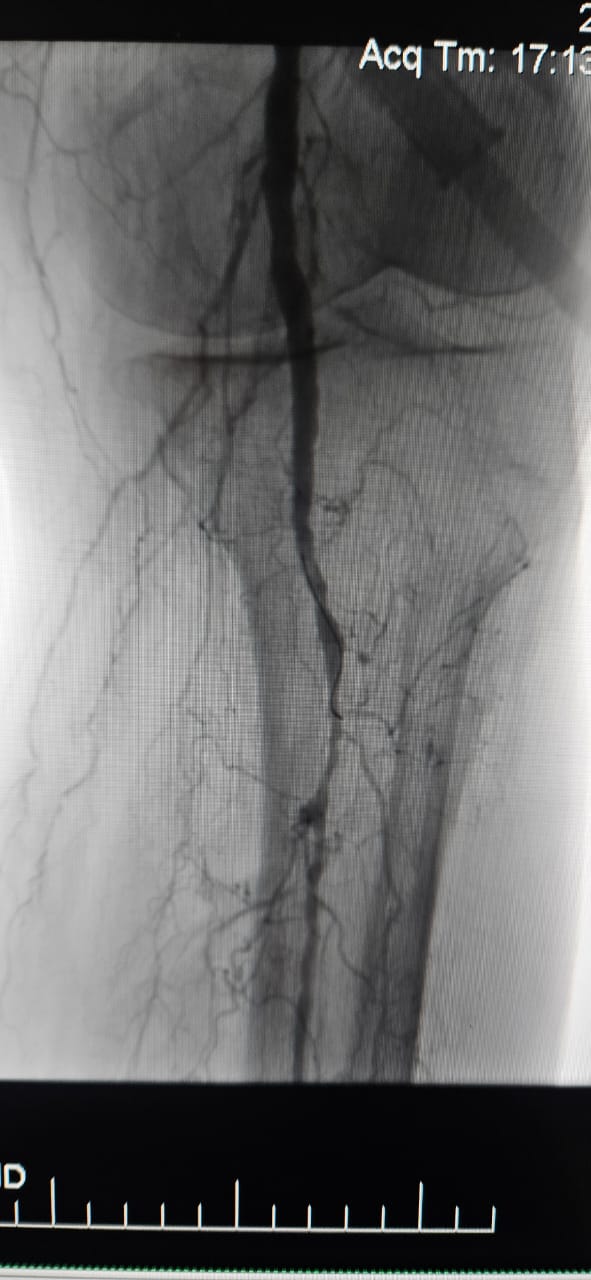

Cieszymy się, że możemy podzielić się udanym przypadkiem ze szpitala w Batumi w stanie Georgia, gdzie 78-letnia pacjentka z krytycznym niedokrwieniem kończyn (CLI) spowodowanym przewlekłym całkowitym niedrożnością tętnicy kończyny dolnej wykazała niezwykłą poprawę kliniczną po leczeniu za pomocą ThorCrack Peripheral IVL Balloon Dilatter Catheter System.

Ten przypadek podkreśla wartość kliniczną litotrypsji wewnątrznaczyniowej (IVL) w leczeniu złożonych przypadków CLI z przewlekłą okluzją o długim segmencie-szczególnie u pacjentów z ciężkim zwapnieniem, gdzie tradycyjne balony lub urządzenia do aterektomii mogą mieć ograniczoną skuteczność.